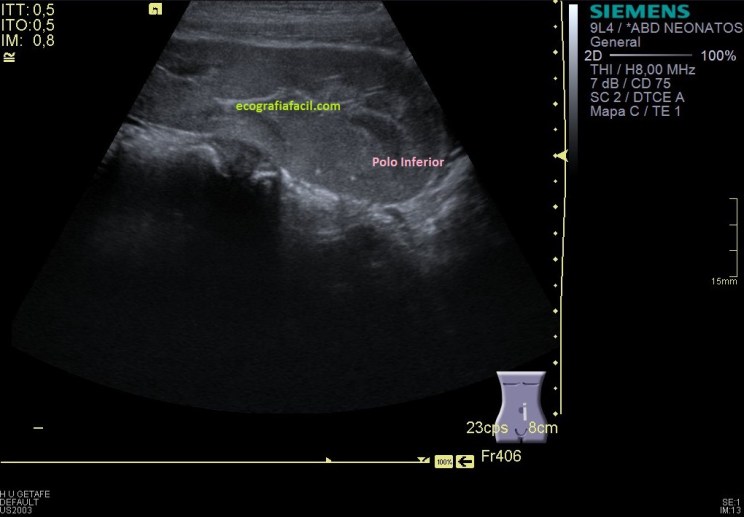

Como en la imagen 1 no he podido ver los polos, tengo que poder demostrarlos aunque tenga que estudiarlos de modo individual, polo superior en una,imagen 2 y polo inferior en otra, imagen 3.

Y nos quedaba buscar el polo superior, imagen 8, buscándolo nos encontramos que este polo superior está unido al polo inferior del RD, sí lo sabía, pero el protocolo de búsqueda de ambos polos renales individualizadamente te garantiza que este tipo de malformaciónes, tipo riñón en herradura, no se escapen. En este caso se ve fenomenal, como ambos polos están, unidos entre sí